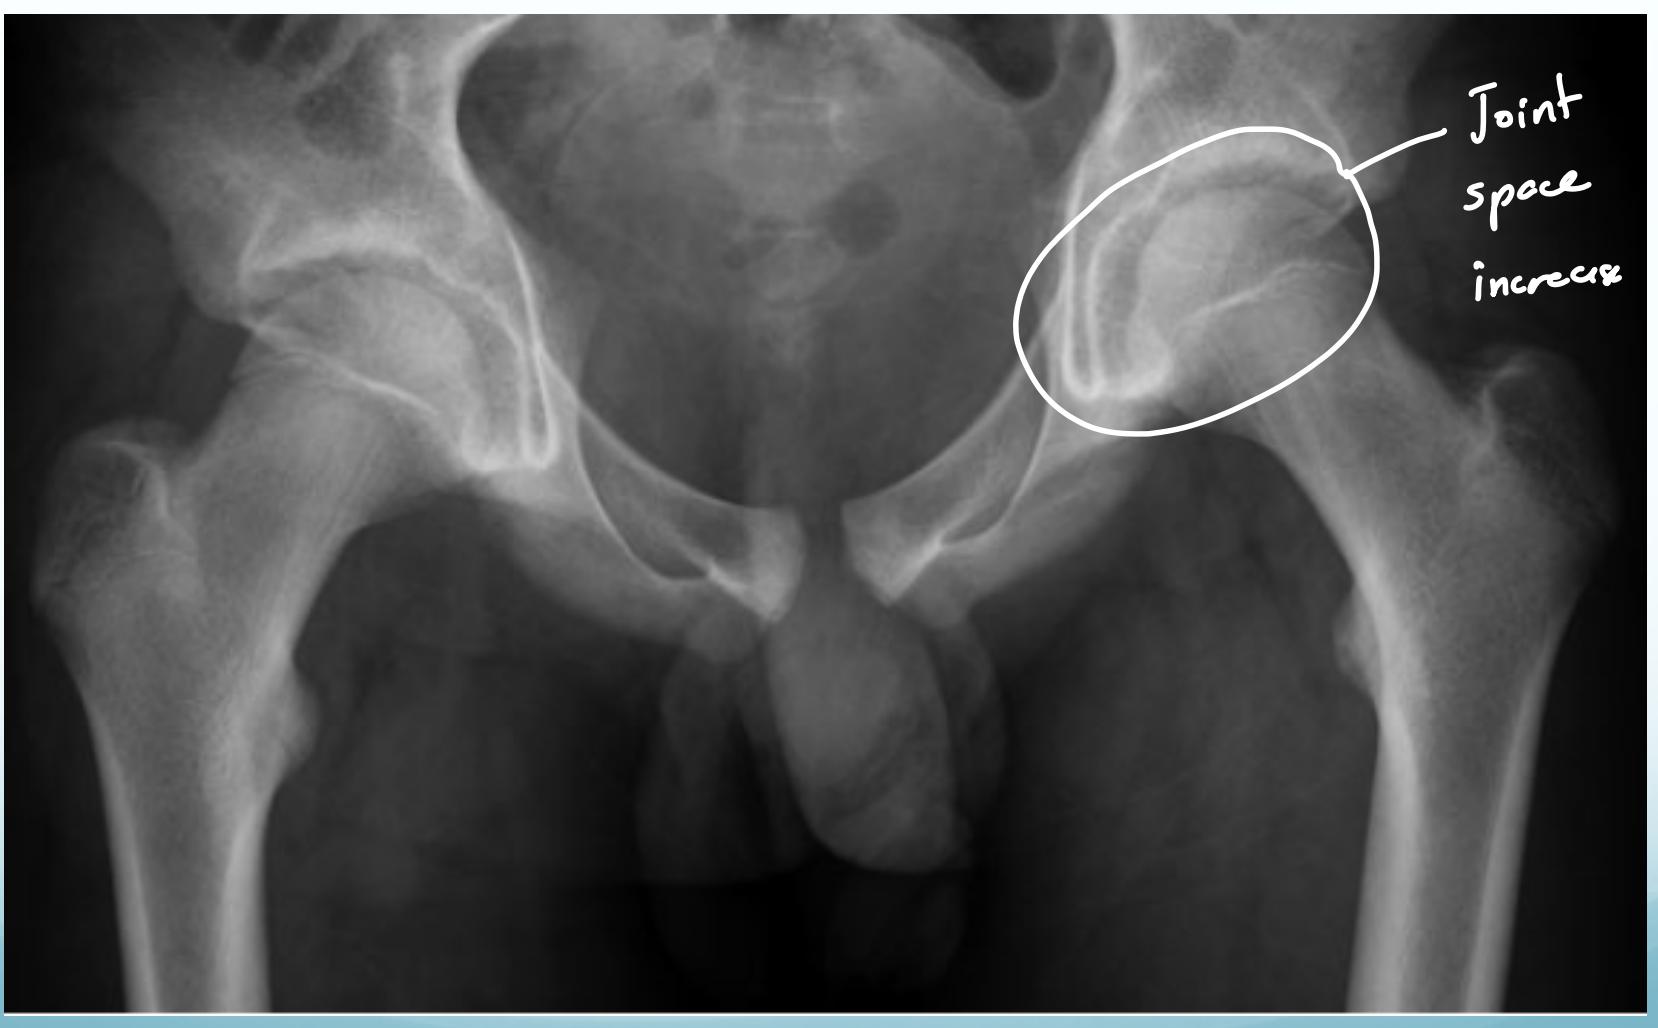

Station 3: Hip Examination

Hip Examination